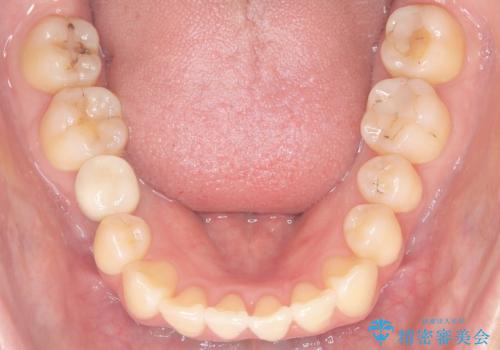

下顎前歯の叢生が整い、右下5番部には機能的かつ審美的なインプラント補綴が完了しました。

咬合全体のバランスも改善し、長期的な安定性が期待される状態となりました。